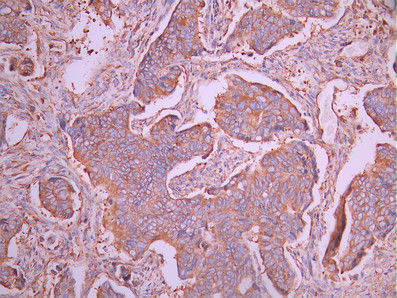

• IHC image of CSB-RA215735A0HU diluted at 1:100 and staining in paraffin-embedded human colorectal cancer performed on a Leica BondTM system. After dewaxing and hydration, antigen retrieval was mediated by high pressure in a citrate buffer (pH 6.0). Section was blocked with 10% normal goat serum 30min at RT. Then primary antibody (1% BSA) was incubated at 4°C overnight. The primary is detected by a Goat anti-rabbit polymer IgG labeled by HRP and visualized using 0.05% DAB.